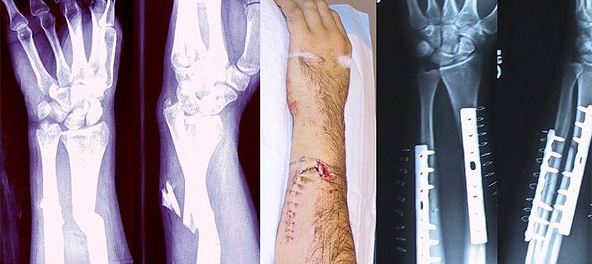

Перело́м ко́сти — полное или частичное нарушение целостности кости при нагрузке, превышающей прочность травмируемого участка скелета. Переломы могут возникать как вследствие травмы, так и в результате различных заболеваний, сопровождающихся изменениями в прочностных характеристиках костной ткани.

Основные принципы лечения переломов не изменились с эпохи античности, хотя современная хирургия и позволила восстанавливать анатомическую структуру костей при сложных, вколоченных, многооскольчатых переломах, переломах, неправильно сросшихся, без восстановления нормального положения кости, и многих других видах травм

Так, например, перелом шиловидного отростка лучевой кости, называется переломом Коллеса. Также к довольно известным типам травм верхней конечности относятся перелом Монтеджа, возникающий при переломе локтевой кости в верхней трети и вывихе головки лучевой кости с повреждением ветви лучевого нерва, и перелом Голеацци, представляющий собой перелом лучевой кости в нижней трети с разрывом дистального радио-ульнарного сочленения и вывихом в этом суставе.